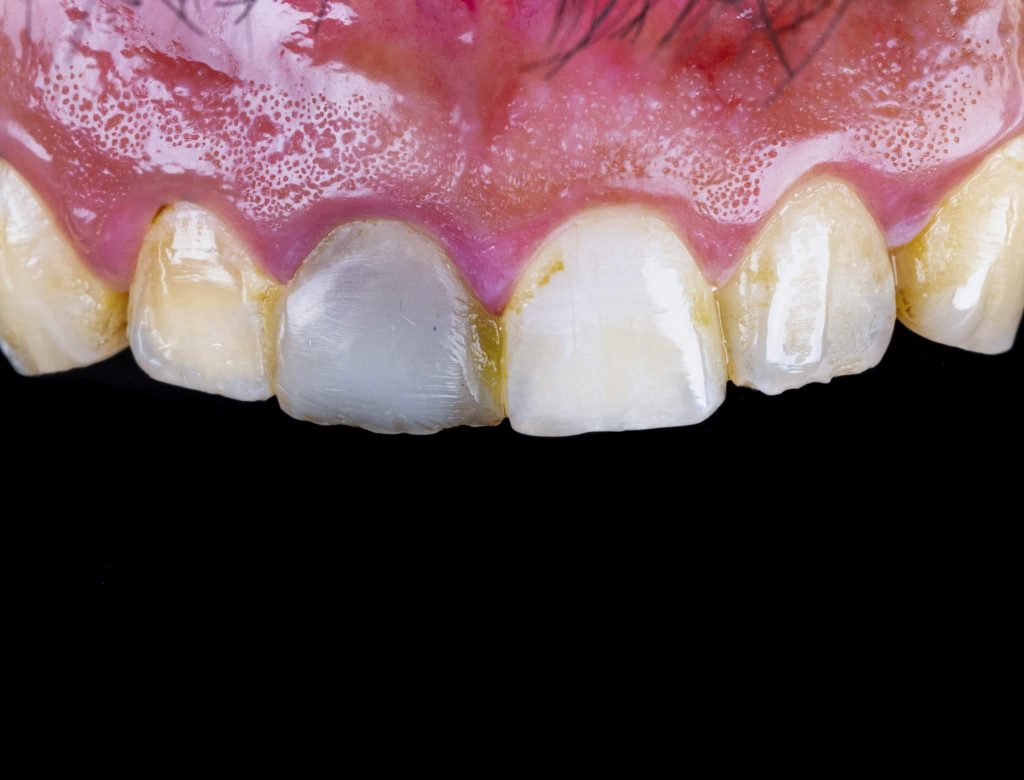

This is a case of discolored right central incisor for a 21 years-old-male patient. He had a history of previous trauma 2 years ago to his tooth and fracture, that was managed with a composite restoration. After clinical examination and x-ray imaging, the tooth was non-vital with periapical lesion.

After discussing the treatment options with the patient, he chose the direct composite veneer. The treatment included endodontic treatment, internal bleaching, direct composite veneer for the right central, and aesthetic reshaping for the laterals and left incisor also by composite restoration. The case completed in 2 sessions.